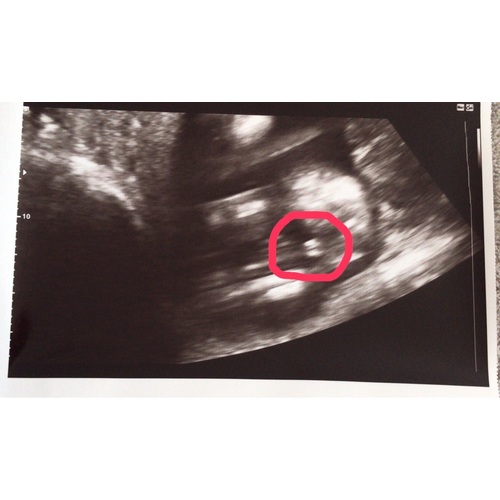

Duidelijk een jongen. Ik krijg een meisje en daarbij zag je duidelijk de hamburger, hier zie je echt balletjes.